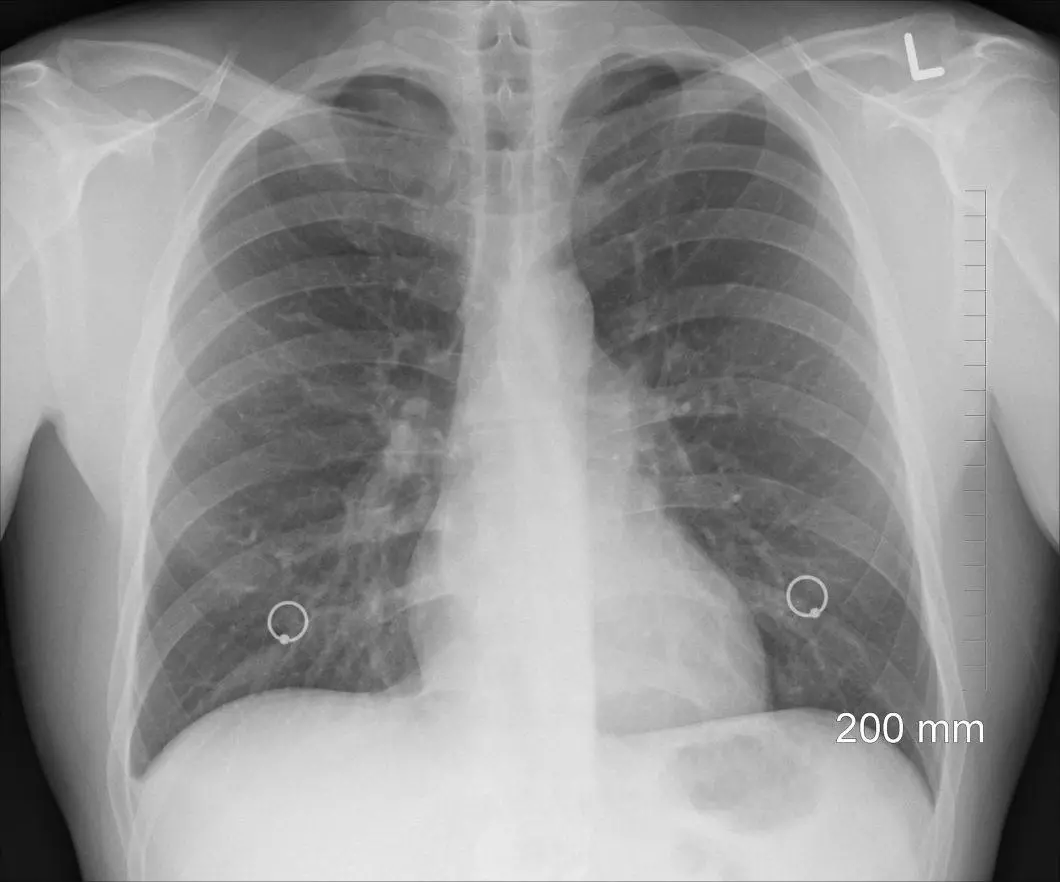

Celles réalisées au niveau du thorax permettent d'observer le coeur et les poumons tout proches. Splendide non ?